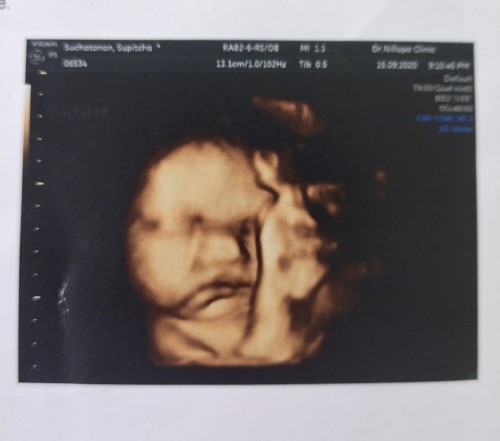

มาอวดรูปตอนซาวด์กันหน่อยค่ะ แม่ๆกำหนดคลอดเดือนไหนบ้างคะ